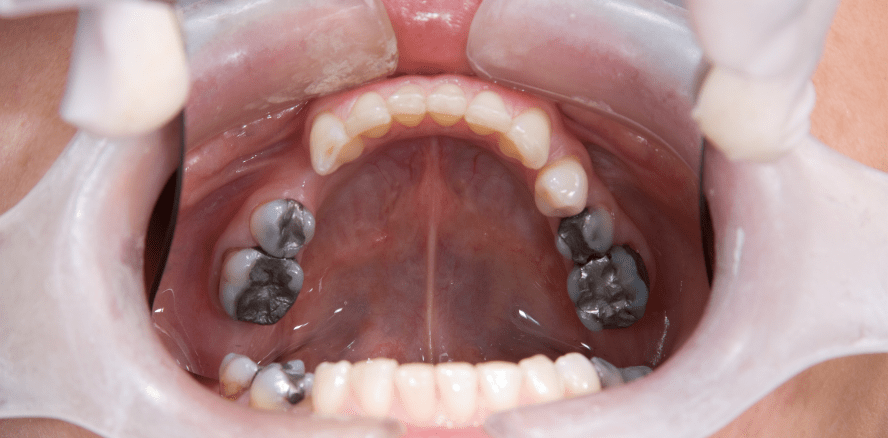

Jede neunte Person in Mecklenburg-Vorpommern erhält bei schadhaften Seitenzähnen eine Amalgamfüllung, in Baden-Württemberg hingegen nur jede 83. Das geht aus einer aktuellen Auswertung des BARMER-Zahnreports hervor, die vor dem Hintergrund des Amalgamverbots der Europäischen Union ab Januar 2025 erarbeitet wurde. Demnach gibt es nach wie vor große regionale Unterschiede beim Einsatz von Amalgam. Die niedrigsten Amalgamanteile bei der Inanspruchnahme von Seitenzahnfüllungen gab es im Jahr 2023 in Baden-Württemberg, Bayern und Hessen mit rund 1,2 beziehungsweise 1,3 und 1,9 Prozent. Spitzenreiter sind Brandenburg, Sachsen und Mecklenburg-Vorpommern mit 8,3 beziehungsweise 8,7 und 11,2 Prozent. „Im Interesse der Versicherten sind vor allem qualitativ hochwertige, zuzahlungsfreie Alternativen für Amalgam als Füllungswerkstoff wichtig. Eine Grundlage dafür ist die von Kassenzahnärztlicher Bundesvereinigung und GKV-Spitzenverband kürzlich erarbeitete Regelung“, sagt der Vorstandsvorsitzende der BARMER, Prof. Dr. med. Christoph Straub. Jedoch müsse der neue gesetzliche Anspruch auf eine zuzahlungsfreie Versorgung ohne Amalgam in den Praxen klar und unmissverständlich kommuniziert werden.

Dem Zahnreport der BARMER zufolge bekamen im Jahr 2023 bundesweit noch 3,5 Prozent der Patientinnen und Patienten in ihren Seitenzähnen eine Amalgamfüllung. Im Jahr 2021 lag dieser Wert noch bei 4,6 Prozent. In dem genannten Zeitraum ergibt sich also eine relative Abnahme von etwa 25 Prozent. Untersucht wurden für diese Werte rund 1,7 Millionen Patienten mit einer Seitenzahnfüllung.

Nach den Daten der BARMER lag der bundesweite Anteil der Praxen, die mindestens eine Amalgamfüllung abrechneten, bei knapp 20 Prozent. Damit können bundesweit mehr als 80 Prozent der Praxen als „amalgamfrei“ bezeichnet werden. Eine alternative Versorgung der Patienten wird demnach offensichtlich schon vor dem Amalgamverbot ab 1. Januar 2025 von einer Vielzahl der Praxen umgesetzt. Welche zuzahlungsfreien Füllungen dort genau angeboten beziehungsweise eingebracht wurden, kann anhand der Daten der BARMER jedoch nicht ermittelt werden. Die regionalen Anteile der Praxen mit Amalgamverwendung reichen für das Jahr 2023 von 8,3 Prozent in Baden-Württemberg bis hin zu 48,2 Prozent in Mecklenburg-Vorpommern. „Die künftig anstelle von Amalgam eingesetzten Alternativwerkstoffe sollten unbedingt wissenschaftlich gut abgesichert sein. Aus medizinischer Sicht sind besonders bei der Haltbarkeit der Füllungen keine Abstriche akzeptabel“, sagt Prof. Dr. Michael Walter von der Technischen Universität Dresden, Autor des BARMER-Zahnreports. Eine qualitativ hochwertige Versorgung für ausnahmslos alle Versicherten müsse angesichts des bevorstehenden Amalgamverbots weiter im Vordergrund der fachlichen Diskussionen zu dem Thema stehen.